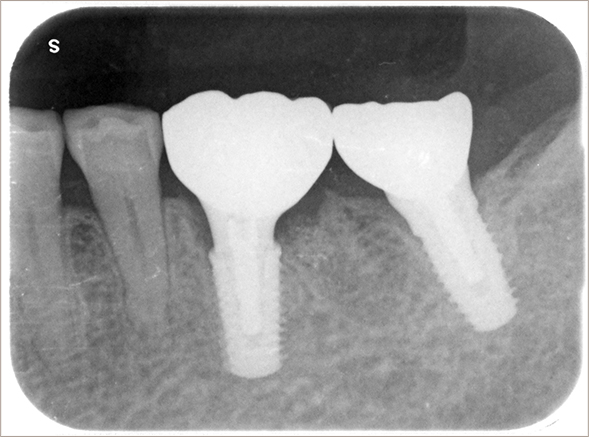

2025年4月10日撮影

インプラント埋入部の骨レベルは埋入時と変わらず、患者様ご自身のメンテナンスも良好で、経過は非常に良く、満足されています。